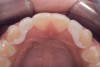

Fig 13. Deficient ridges in the areas of the missing lateral incisors.

Figure 13

Fig 14. Occlusal view. Some form of augmentation will be needed if implants are considered.

Figure 14